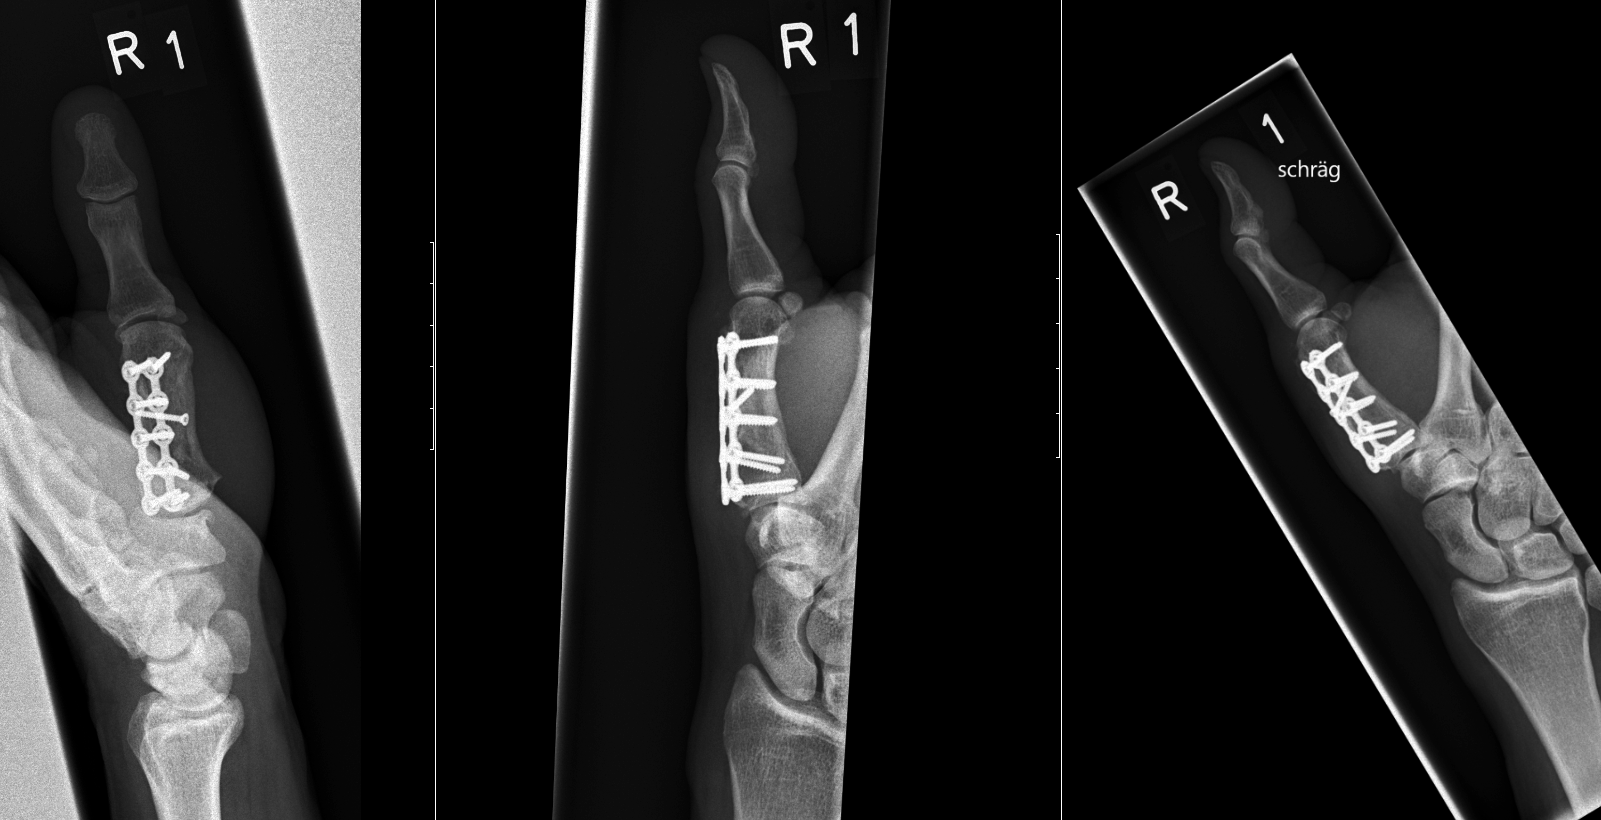

Case 1:

A 64-year-old male suffered a multi-fragmentary fracture of his right thumb metacarpal (Fig 1). An adapted 12-hole strut plate from the variable angle locking hand system was the implant of choice for fixation (Figs 2 - 4).

The strut plate provided good stability in a comminuted extraaricular fracture pattern and enables immediate mobilization. Bone callus formation was not witnessed during the healing process.